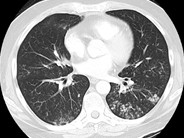

Reactive marrow: infection post-chemotherapy - 2.

The bone marrow aspirate from this patient is mildly hypocellular with increased histiocytes consistent with a reactive process. Blasts are not increased, suggesting that the patient may have responded to therapy.